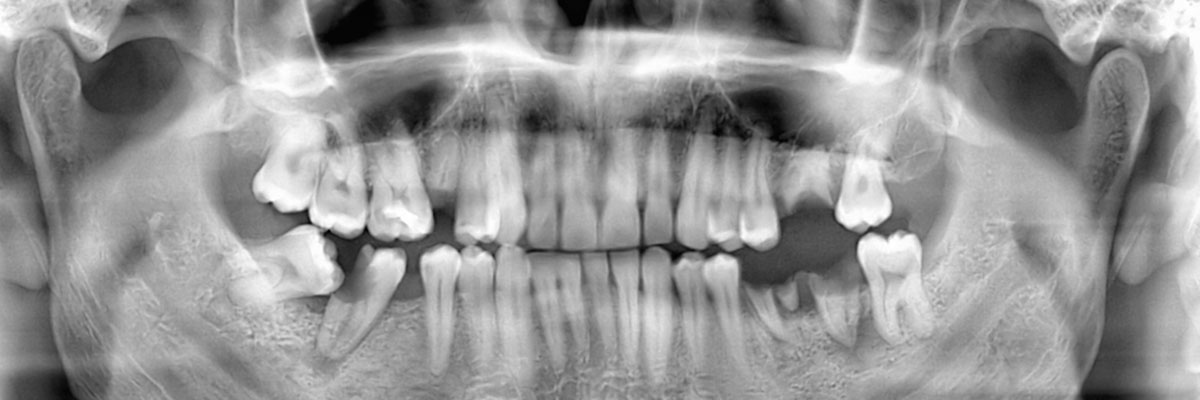

We recommend that you call 714-677-9452 and schedule an appointment with our dental office as soon as your tooth has either fallen or been knocked out. During your appointment, we will examine your gums, take X-rays, and make a recommendation as to which tooth replacement option will be best suited for your needs. Acting on this quickly will help in restoring your appearance and oral health.